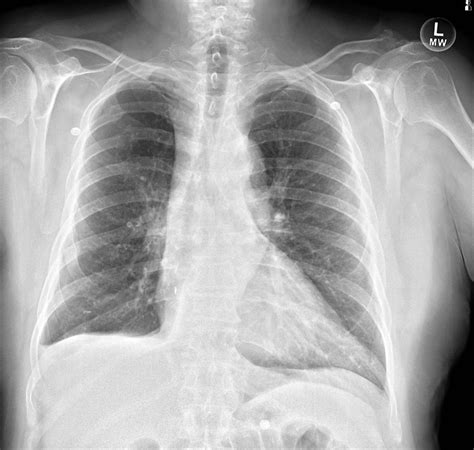

• Cancer: Both primary bone cancers (e.g., osteosarcoma) and metastatic cancers (e.g., breast cancer spreading to the bone) can cause bony lesions.

• Fractures: Increased risk of fractures, especially in cases of metastatic lesions.

• Imaging Studies: X-rays, CT scans, MRI, and bone scans are commonly used to visualize the lesion and determine its characteristics.